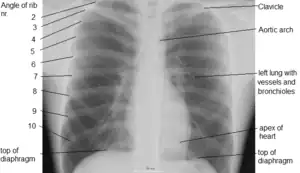

Thorax

The thorax (pl.: thoraces or thoraxes)[1] or chest is a part of the anatomy of mammals and other tetrapod animals located between the neck and the abdomen.[2][3] In insects, crustaceans, and the extinct trilobites, the thorax is one of the three main divisions of the creature's body, each of which is in turn composed of multiple segments.

The human thorax includes the thoracic cavity and the thoracic wall. It contains organs including the heart, lungs, and thymus gland, as well as muscles and various other internal structures. Many diseases may affect the chest, and one of the most common symptoms is chest pain.

In humans and other hominids, the thorax is the chest region of the body between the neck and the abdomen, along with its internal organs and other contents. It is mostly protected and supported by the rib cage, spine, and shoulder girdle.

The contents of the thorax include the heart and lungs (and the thymus gland); the major and minor pectoral muscles, trapezius muscles, and neck muscle; and internal structures such as the diaphragm, the esophagus, the trachea, and a part of the sternum known as the xiphoid process. Arteries and veins are also contained – (aorta, superior vena cava, inferior vena cava and the pulmonary artery); bones (the shoulder socket containing the upper part of the humerus, the scapula, sternum, thoracic portion of the spine, collarbone, and the rib cage and floating ribs).